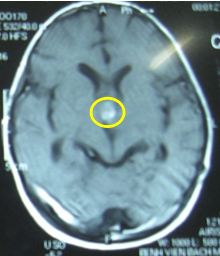

Sau xạ trị gia tốc 3 tuần (đợt 1): Hình ảnh chụp cộng hưởng từ (MRI) sọ não:kích thước u thu nhỏ lại rất nhiều (trong vòng màu vàng)